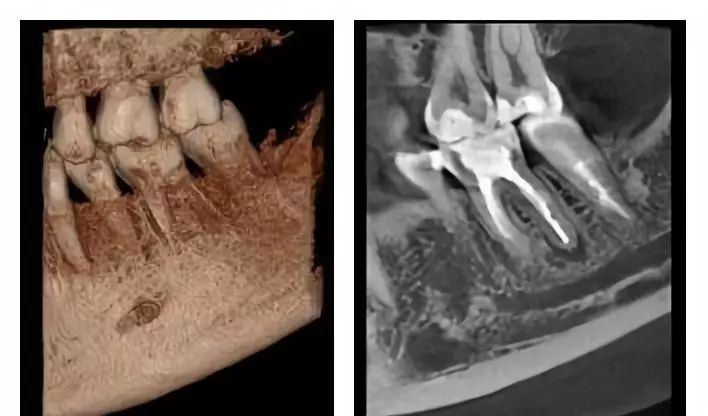

口腔CT是圍繞人體的一段容積螺旋式的采集數(shù)據(jù)。口腔CT與常規(guī)CT的本質(zhì)區(qū)別在于前者獲得的是三維信息,而后者獲得的是二維信息。口腔CT機(jī)提高了掃描速度,掃描覆蓋面廣,無間隙采集容積數(shù)據(jù),便于各種方式、各種角度的影像重建,且可以任意地、回顧性重建。視野選擇與圖像合成方面,口腔CT機(jī)比常規(guī)CT有著明顯的優(yōu)勢。它的空間分辨率高,對下頜骨、下頜神經(jīng)管、顳下頜關(guān)節(jié)解剖結(jié)構(gòu)、牙齒根管系統(tǒng)成像質(zhì)量更好。以下介紹三維口腔CT機(jī)的臨床應(yīng)用特點是什么?

通過三維重建并輔以軸位和其它層面圖像,便于醫(yī)生準(zhǔn)確了解埋伏牙,多生牙,囊腫,腫瘤等的形態(tài)、位置、鄰牙及臨近解剖結(jié)構(gòu)的關(guān)系。